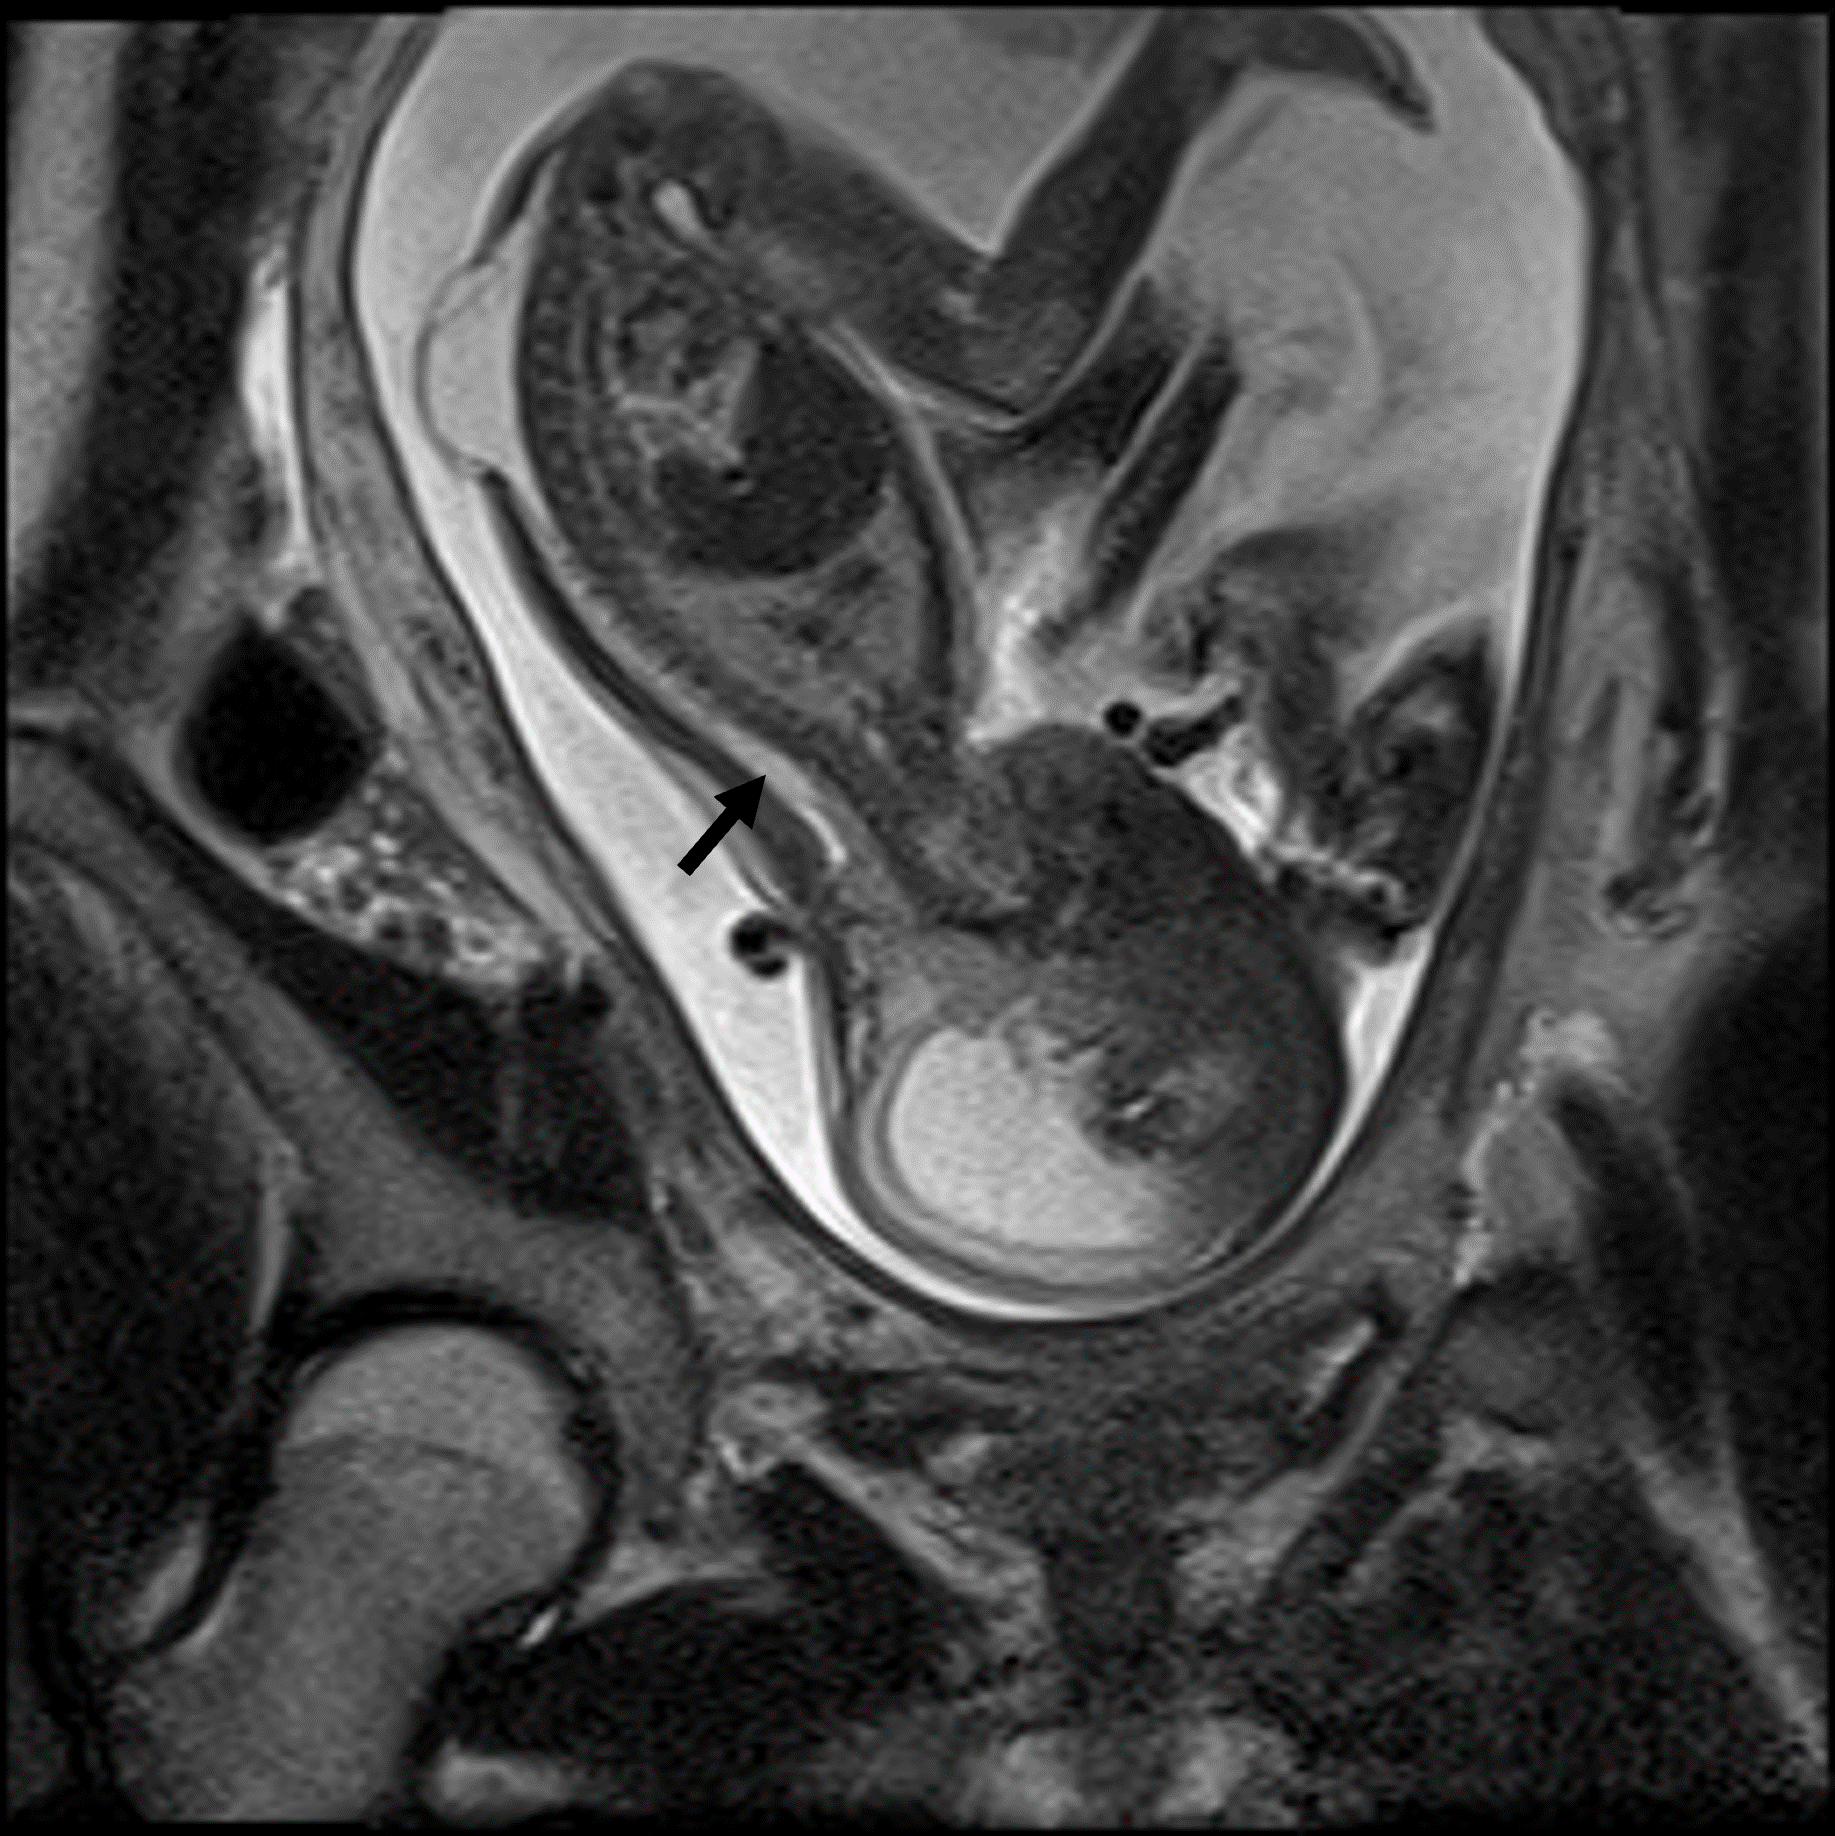

Das fetale MRT (Magnetresonanztomographie) ist ein strahlungsfreies Verfahren, mit dem wir Organe und Strukturen Ihres ungeborenen Kindes besonders detailreich darstellen. Es ergänzt die pränatale Ultraschall-Diagnostik und hilft, Fragestellungen präzise zu klären und die weitere Betreuung zu planen.

- Abklärung von Auffälligkeiten im Ultraschall, z. B. Gehirn, Wirbelsäule, Lunge, Bauchorgane

- Beurteilung von Organreife und Entwicklung, wenn die Sicht im Ultraschall eingeschränkt ist (z. B. mütterlicher Body-Mass-Index, Lage des Kindes)

Unsere Neuroradiologen arbeiten eng mit Pränatalmedizinern, Neonatologen, Pädiatern und Chirurgen zusammen. Modernste Geräte und spezialisierte Protokolle sorgen für hohe Bildqualität – auch bei kindlichen Bewegungen.